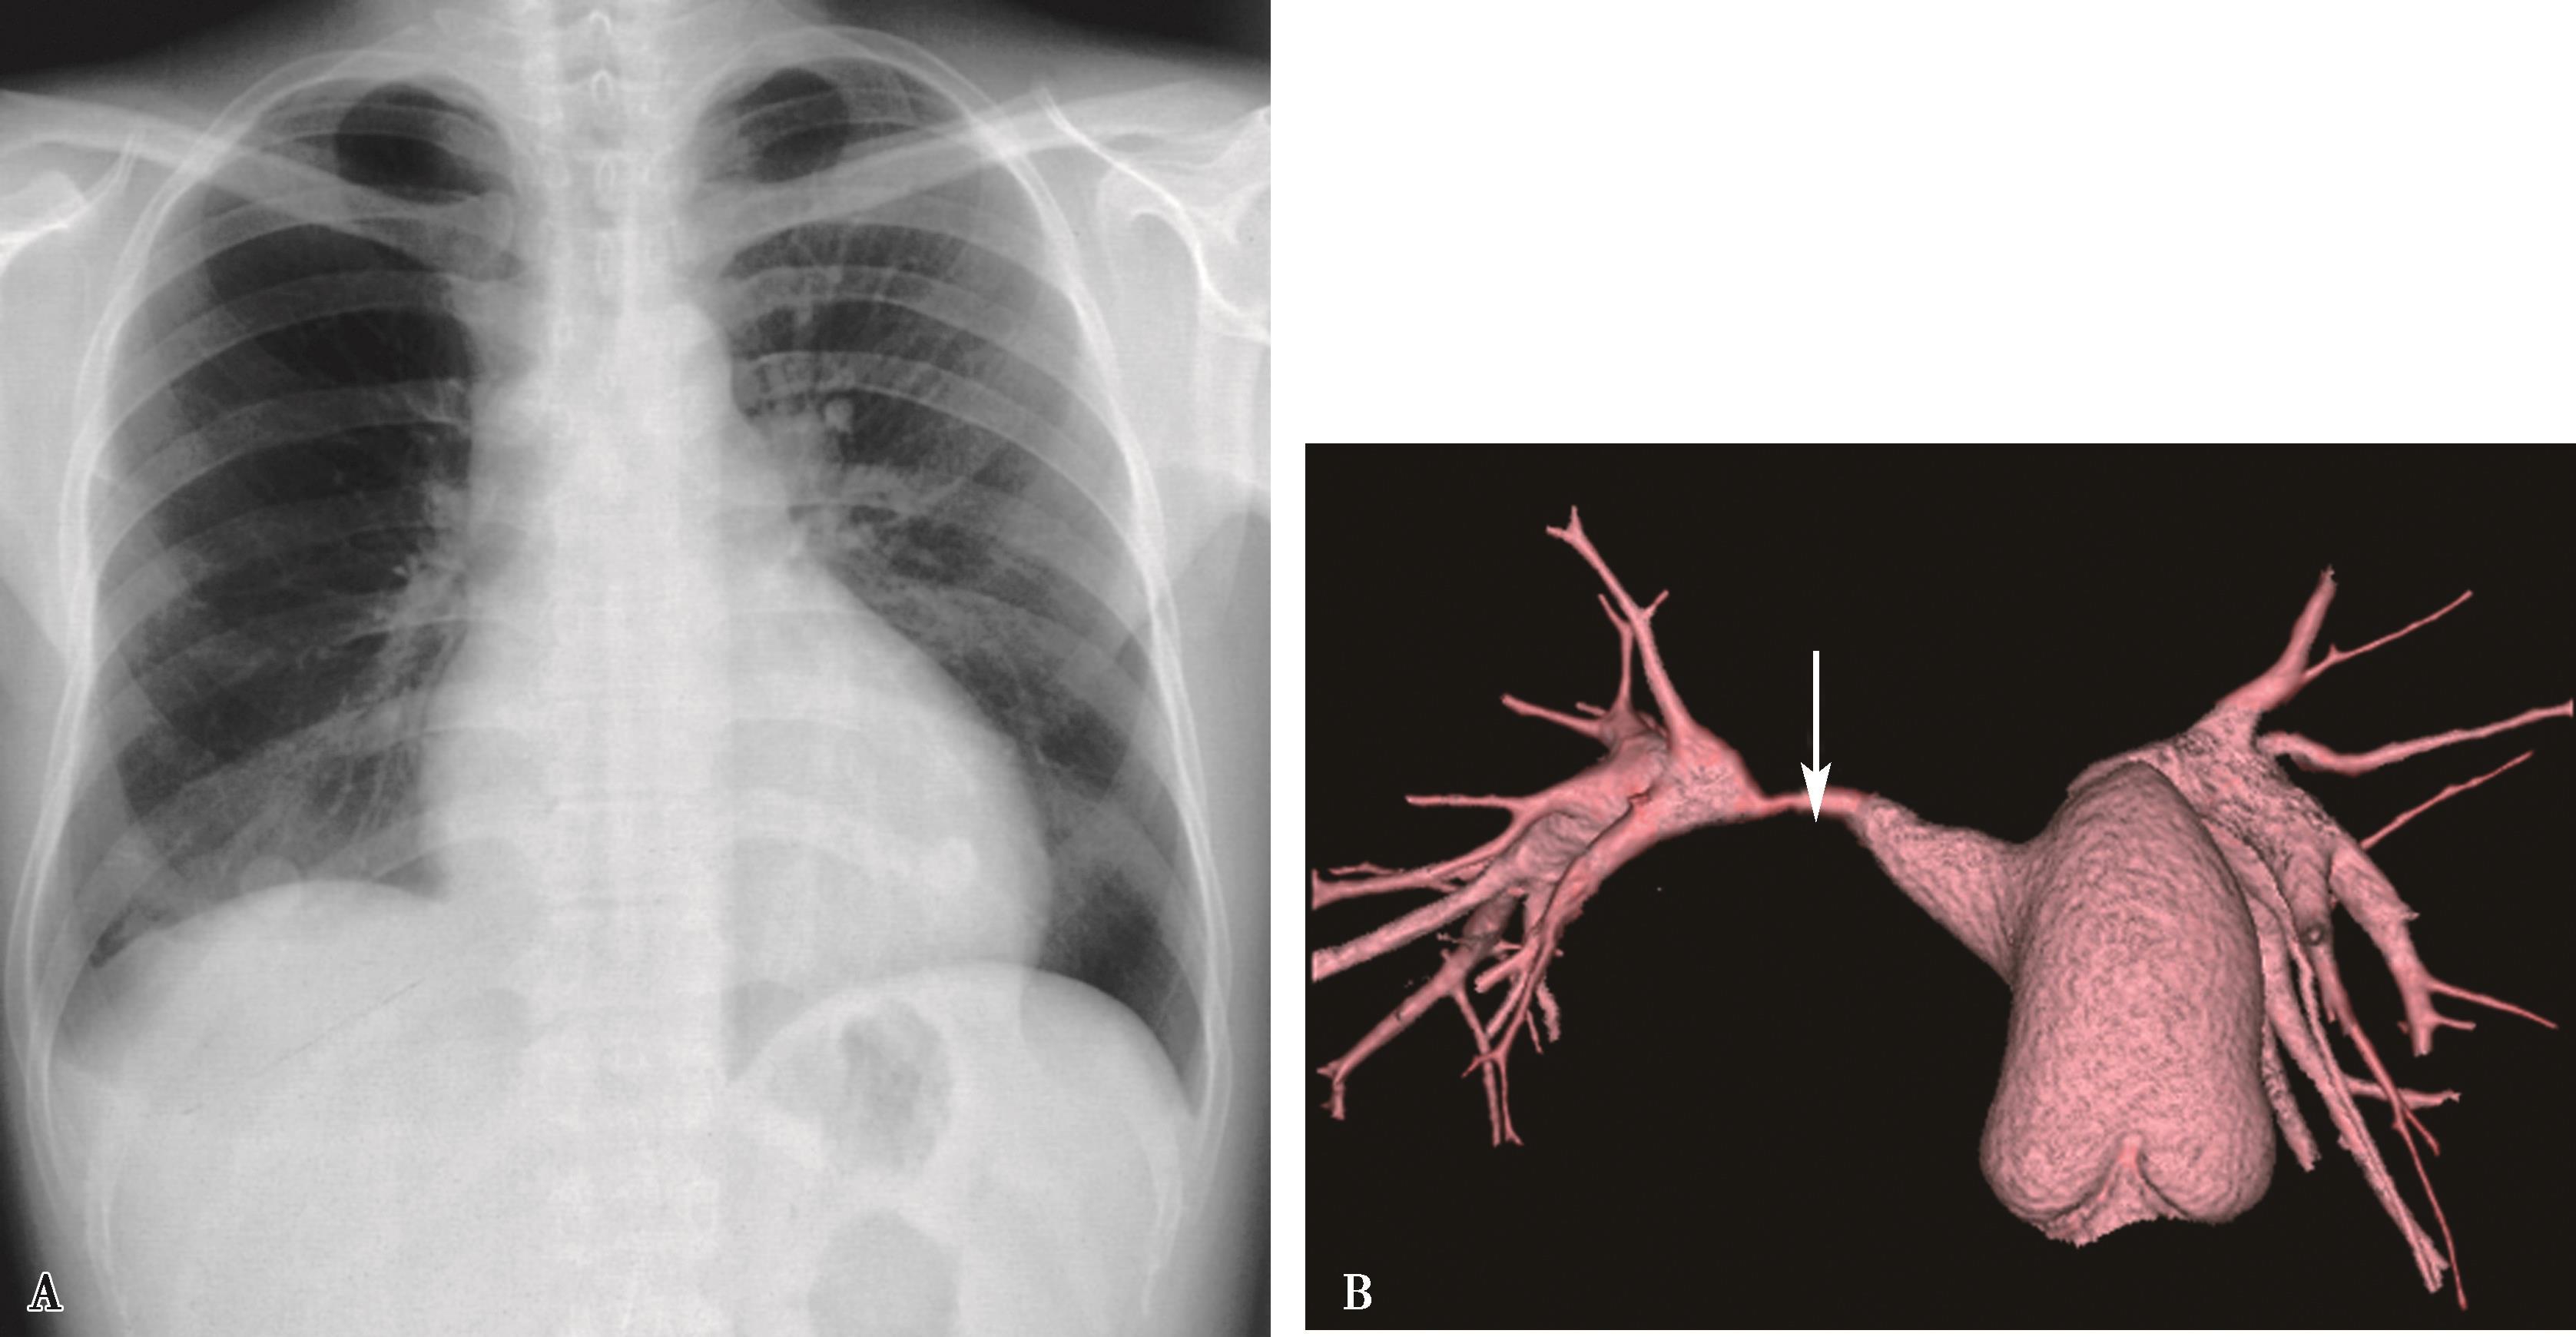

图7-2-4 女,37岁,大动脉炎(肺动脉型),右肺动脉重度狭窄。右侧肺血减少

A.心脏远达,右肺血减少,右心室增大;B.CTPA三维重建(VR),示右肺动脉重度狭窄(↑)